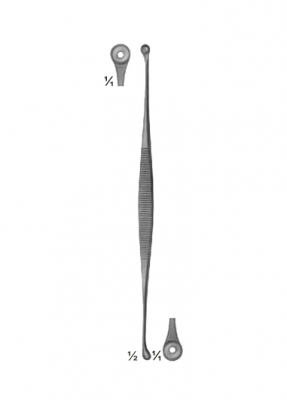

The AE 01 2179 Extracting Forceps are a premium-grade surgical instrument designed to provide exceptional precision, strength, and comfort for a wide variety of clinical and surgical applications. This model is an ideal companion to scalpels, dura knives, and comedone extractors, offering the control and reliability necessary for delicate and high-precision procedures.

Manufactured from high-quality surgical stainless steel, the AE 01 2179 is resistant to rust, corrosion, and stains, ensuring a long service life even under frequent sterilization cycles. The material’s exceptional strength allows the forceps to maintain proper alignment and grip strength over time, guaranteeing consistent performance in demanding surgical environments. The instrument features a smooth, polished finish that not only enhances its professional appearance but also reduces surface porosity, making cleaning and sterilization more effective and helping to maintain strict hygiene standards.

The precision-crafted jaws of the AE 01 2179 are available with fine serrations or a smooth grip, depending on the application. Serrated jaws offer a secure hold on tissues, sutures, or surgical materials without excessive slippage, while smooth jaws are ideal for handling delicate or fragile structures without causing trauma. The tapered tips enable access to confined areas, making this forceps suitable for use in microsurgery, dermatology, and neurosurgical work.

The ergonomic handle design ensures a comfortable grip, minimizing hand fatigue during lengthy procedures. The hinge mechanism operates smoothly, allowing controlled opening and closing with minimal effort, which is crucial for maintaining steady hand movements during precision work.

This forceps is fully autoclavable and complies with international surgical instrument standards. It is suitable for use alongside scalpels for securing tissues during incisions, with dura knives for handling the dura mater in neurosurgery, and with comedone extractors in dermatological treatments.